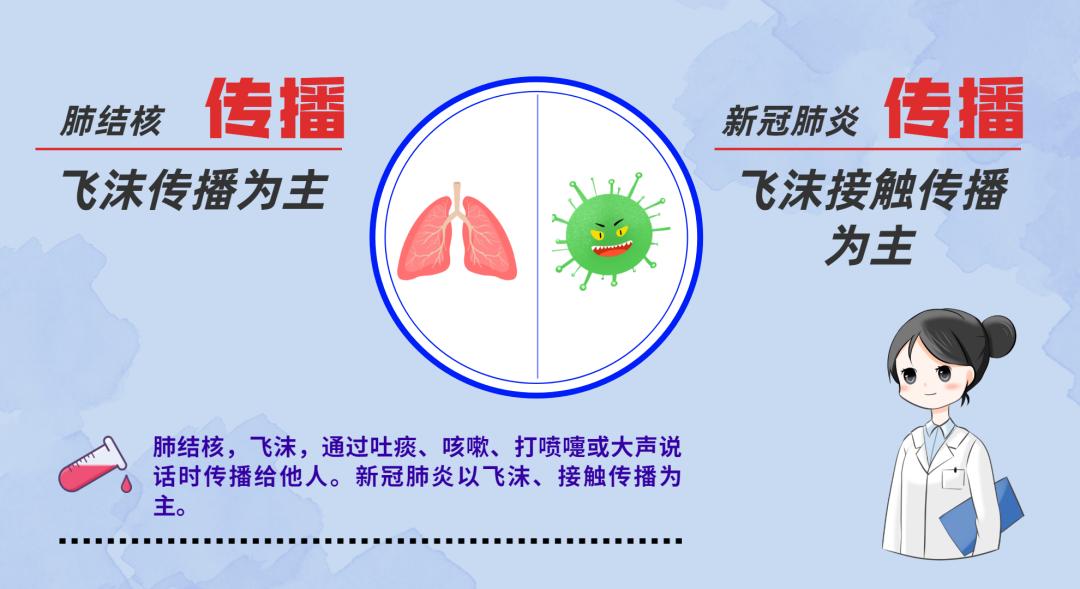

肺结核是怎么传播的?

1.肺结核是呼吸道传染病,容易发生传播。

2.结核菌通过肺结核病人咳嗽、咳痰、打喷嚏播散到空气中,健康人吸入带有结核菌的飞沫即可能受到感染。

3.与肺结核病人共同居住,同室工作、学习的人都是肺结核病人的密切接触者,有可能感染结核菌,应及时到医院去检查排除。